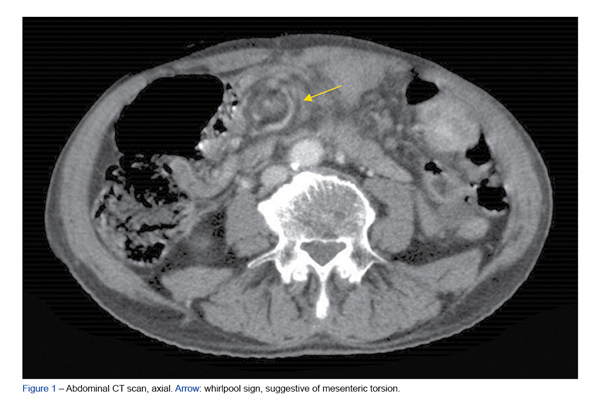

Os schwanomas mesentéricos são tumores benignos raros com origem nas células de Schwann do mesentério. Divertículos ileais ...